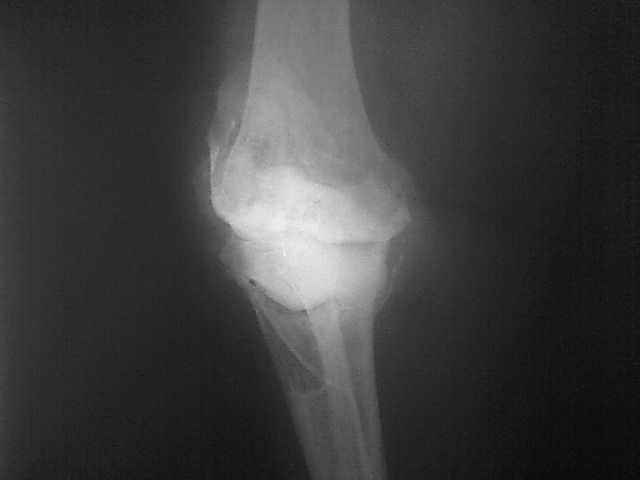

Уважаемые коллеги, прошу Вашего совета по тактике лечения. Женщина 1952 г.р., оперирована в 2006, в одной клинике установлен эндопротез правого коленного сустава, через год нестабильность обоих компонентов, доктор выполняет ревизию обычным протезом с задним стабилизатором. В октябре 2008 - нестабильность, свищ. В другом стационаре все удалено, спейсер с гентамицином, длинный курс антибиотиков. Коллатеральных связок нет. Собственная связка надколенника цела. До удаления протеза - выраженная смешанная контрактура. Сейчас свищей нет, анализы в порядке.

Планы: Стоит выбор 1) Обычный hinge с цементными ножками, вставками под тибиальным и бедренным компонентами с импакционной костной пластикой аллокостью с применением сеток для удержания трансплантата на tibia; 2) Онкологический hinge - с замещением проксимальной голени и сохранением бедра; 3 - артродез.

Мне очень хотелось узнать мнение коллег на предмет - если ставить простой hinge с костной пластикой - стоит ли использовать только костную крошку или необходим структурный костный аллотрансплантат? Есть ли у кого-то положительный опыт таких операций? Душа у меня не лежит использовать онкологическим протез для голени, т.к. пациентка слишком молода и сохранена собственная связка надколенника.

Артродез тоже потребует определенных усилий. Костный дефект очень большой....